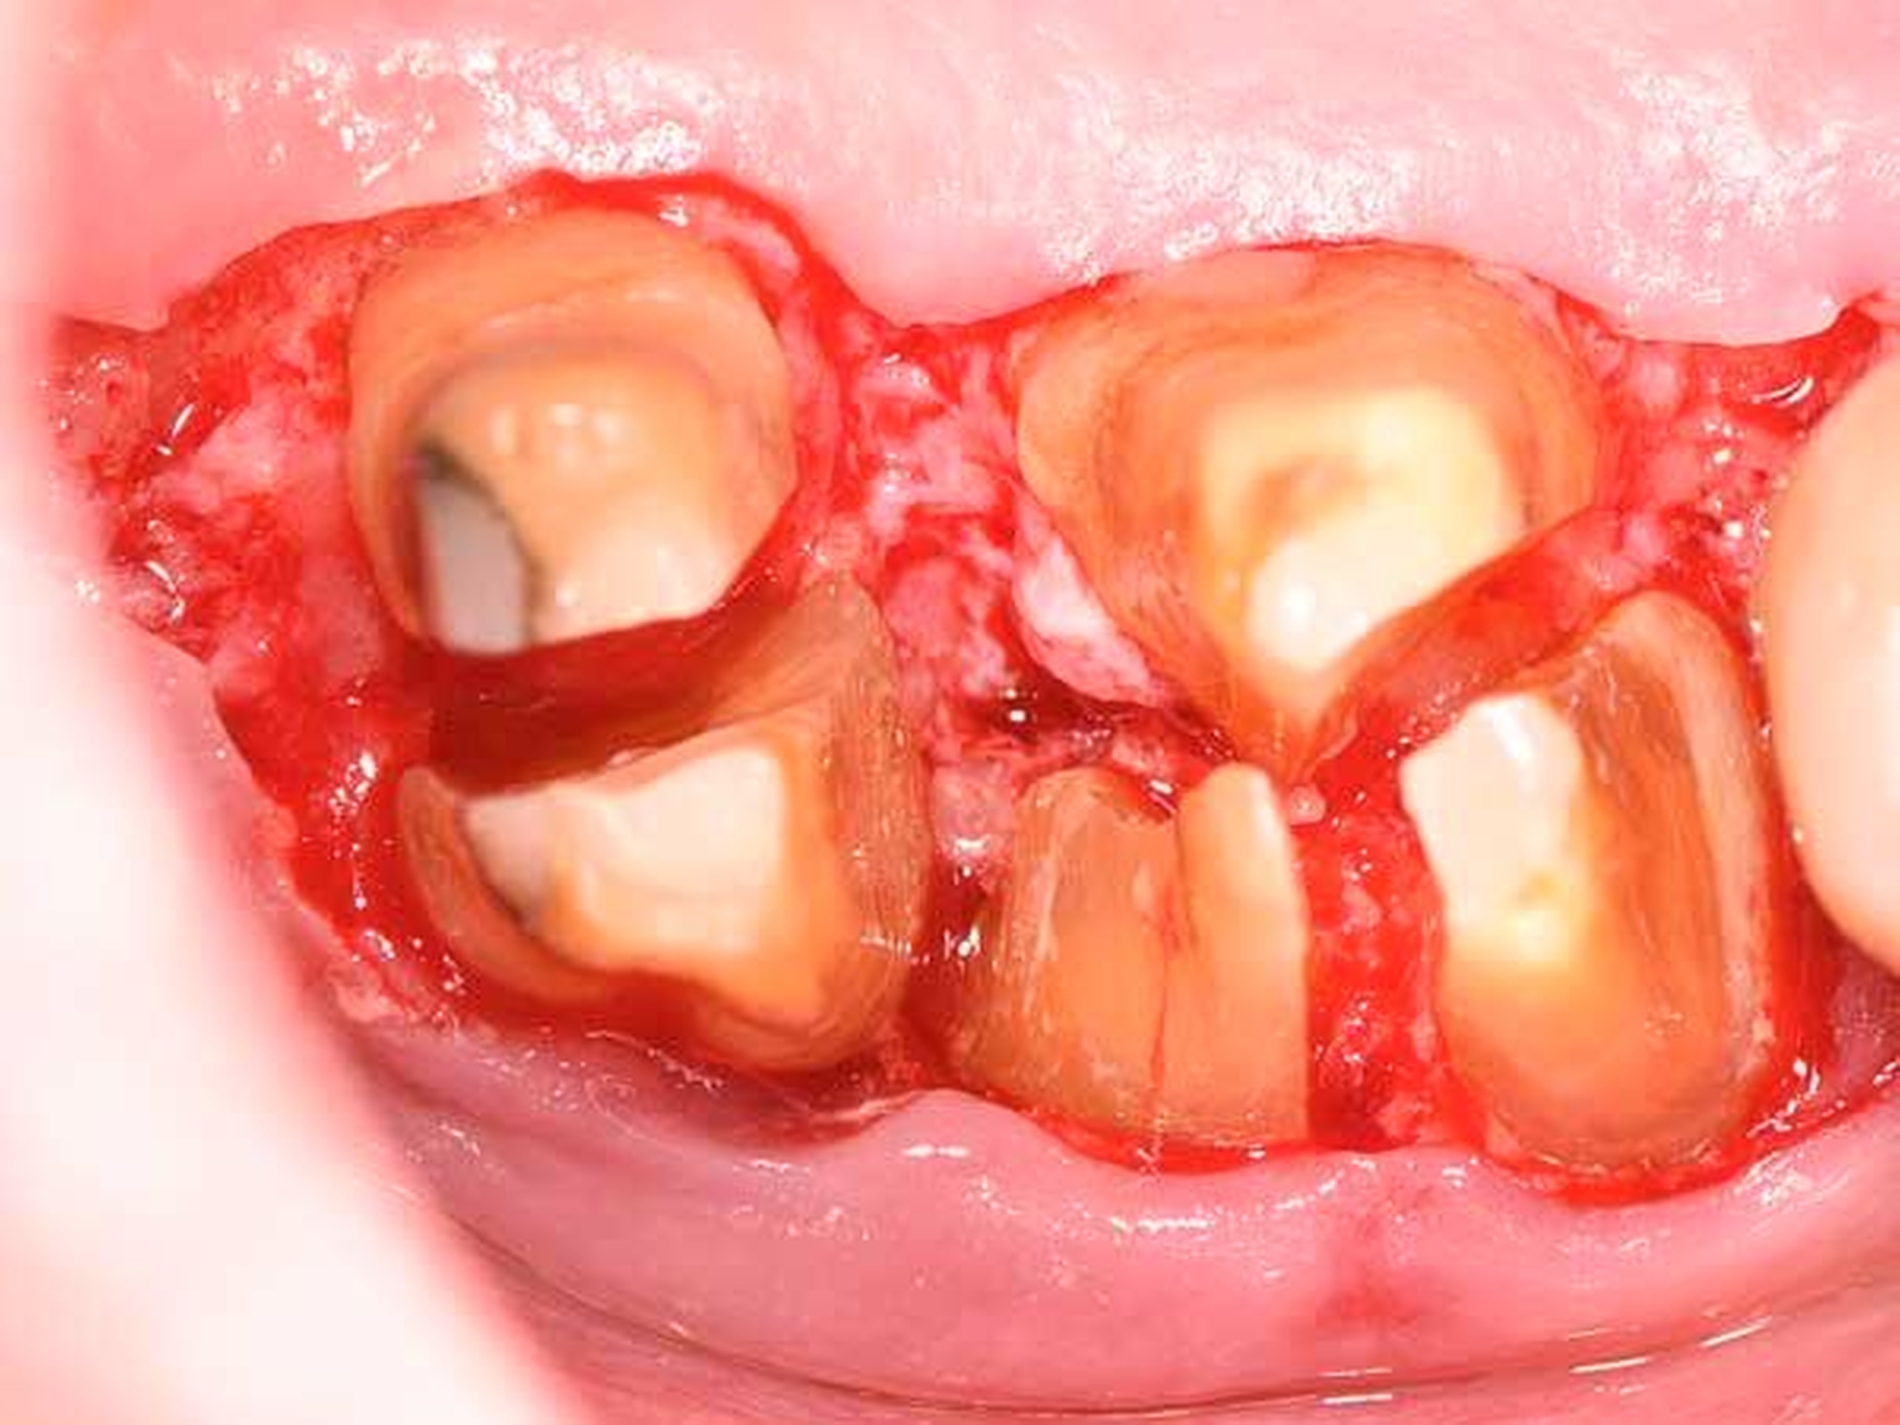

Daher gewinnen gerade im posterioren Oberkiefer oder bei Vorliegen einer durchgängigen Furkation resektive Maßnahmen wie die Amputation einer oder mehrerer Wurzeln (Abbildung 8b bis 8d), die Prämolarisierung sowie die Tunnelierung wieder an Bedeutung. Diese Maßnahmen sind klinisch herausfordernd, da neben einer hochwertigen parodontologischen Versorgung eine adäquate endodontologische Therapie und eine sinnvolle restaurative Versorgung für den Langzeiterfolg notwendig sind. Nachdem Autoren aus Italien [Carnevale et al., 1998] und den USA [Fugazzotto, 2001] schon länger von hervorragenden Überlebensraten wurzelamputierter Molaren berichtet haben, liegen nun auch aus Deutschland retrospektive Daten über bis zu 30 Jahre vor, nach denen ein Wurzel-amputierter Molar eine mediane Überlebenszeit von etwa 20 Jahren aufweist [Derks et al., 2017].